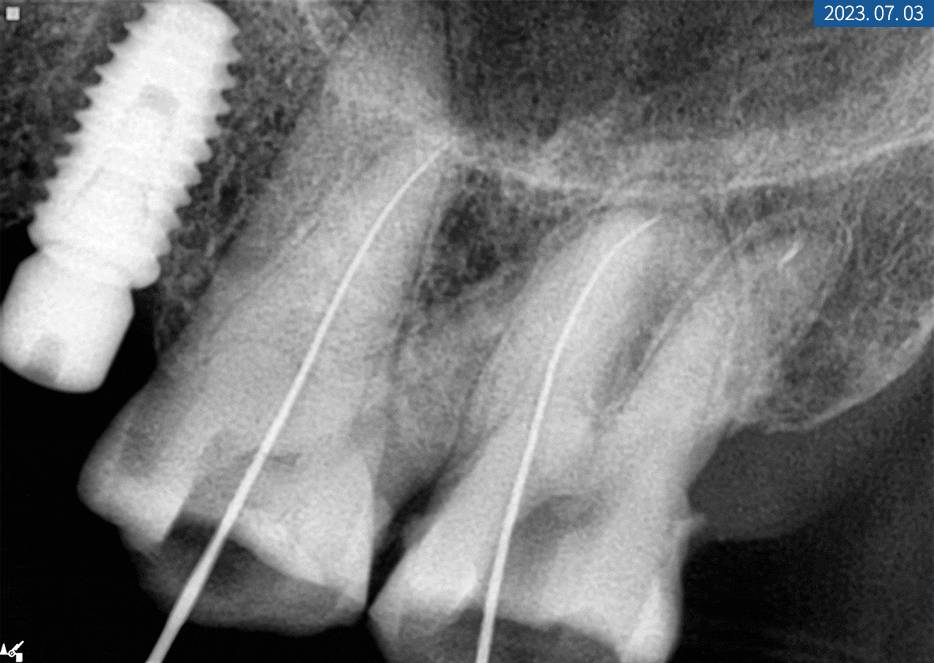

먼저 교합면을 삭제한 뒤 근관을 찾고 발수를 하고

근관장 측정 검사를 하면서 뿌리를 확대했습니다.

마무리로 충분히 세척하고 충전재 수복 후

치아 본을 뜬 다음 크라운까지 씌워드렸습니다.

신경치료중인 환자분의 치근단 X-ray